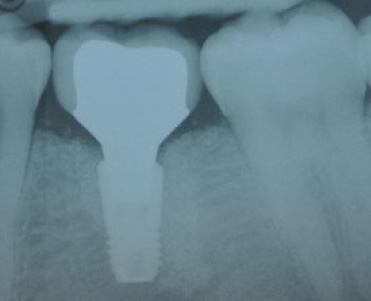

Des piliers d'implants usinés avec profil d'émergence anatomique. Emplacement des implants en prévision de la restauration finale!